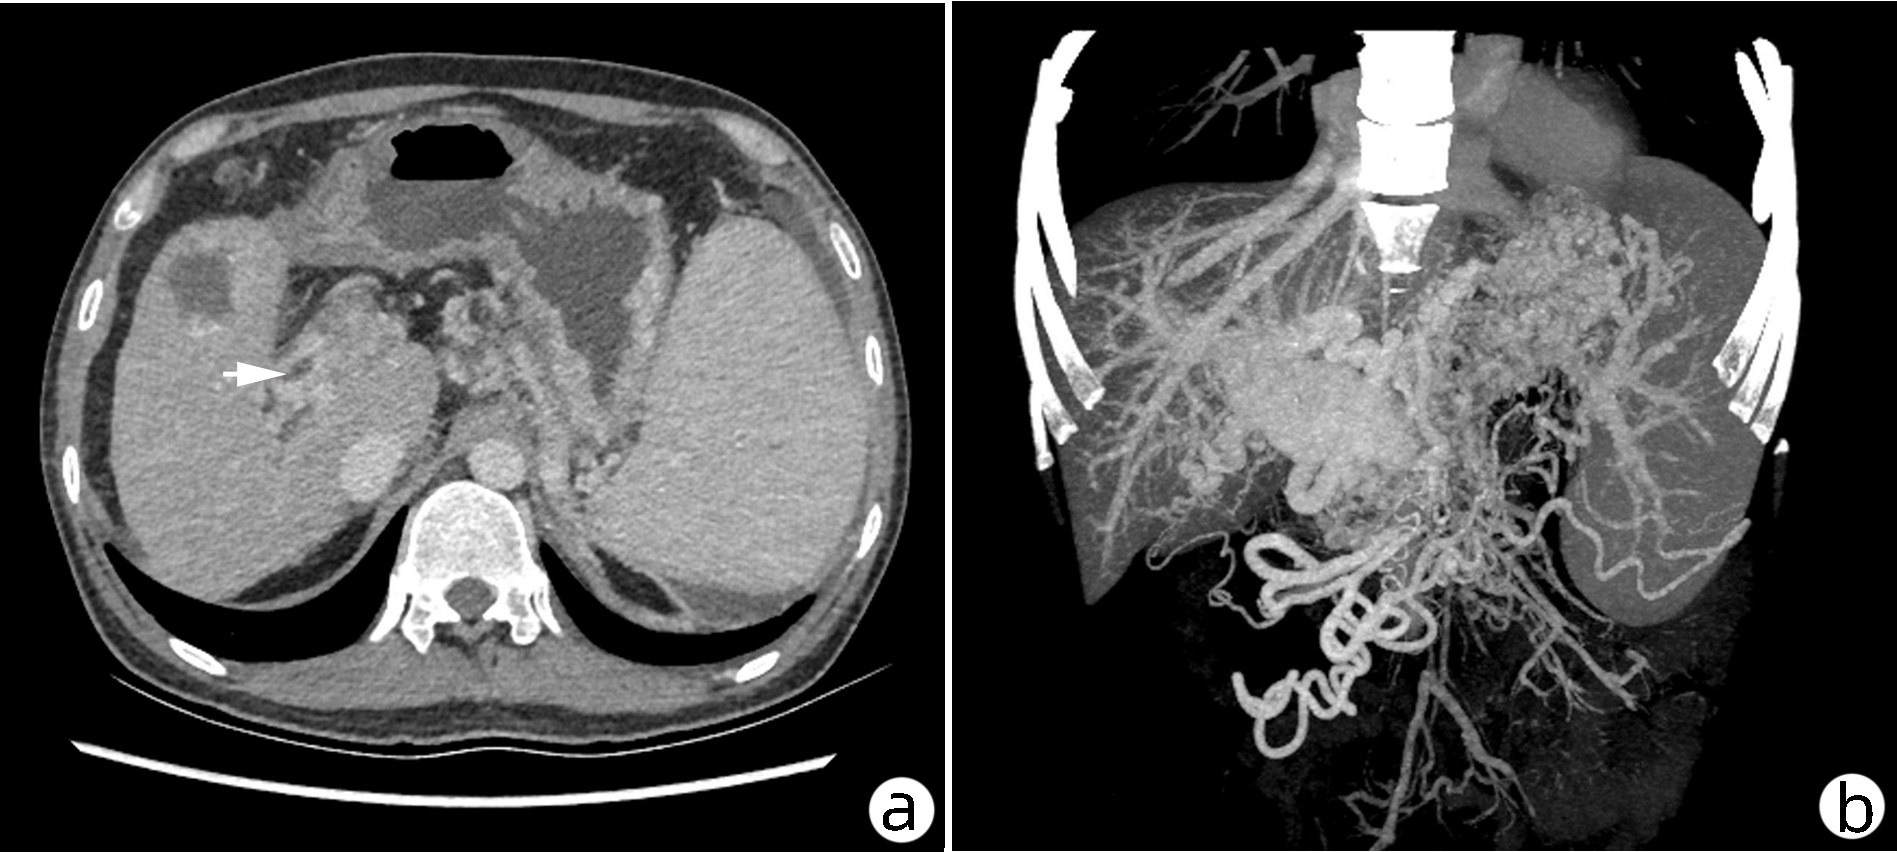

Research advances in congenital extrahepatic portosystemic shunt

Abstract(1666) HTML (1247) PDF (2399KB)(127)

Abstract:

Congenital extrahepatic portosystemic shunt (CEPS) is also called Abernethy malformation, with the manifestation of congenital abnormal anastomosis between the portal vein and the inferior vena cava. CEPS is extremely rare in clinical practice and has diverse clinical symptoms, which often leads to missed diagnosis and misdiagnosis. This article reviews the pathogenesis, classification, clinical manifestation, diagnosis, and treatment of CEPS, so as to improve the awareness of this disease and provide a reference for further standardization of its diagnosis and treatment process in the future.